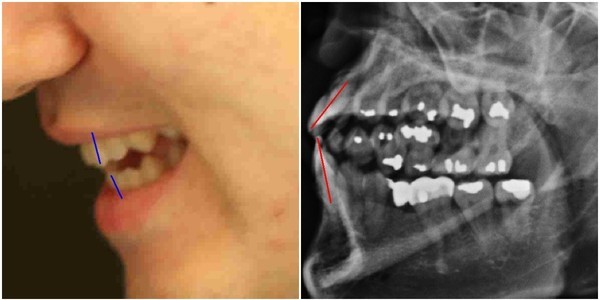

최근 한 인터넷매체는, 박주신씨 병역비리 의혹의 핵심 쟁점 중 하나인 ‘치아 엑스레이’와 관련된 사안을 기사화하면서, 서울시 관계자의 발언을 함께 실었다. 해당 기사가 전한 서울시 관계자의 태도는 매우 고압적이었다.

- ▲ 박주신씨 명의의 구외 엑스레이(치아 엑스레이)와 주신씨의 치아상태를 볼 수 있는 실물 사진 비교, ⓒ 뉴데일리DB

- ▲ 박주신씨 명의 피사체의 치아 상태를 볼 수 있는 치아 엑스레이. ⓒ 뉴데일리DB(차기환 변호사 제공)

기사에 따르면, 서울시 관계자는 박주신씨 명의의 치아 엑스레이 의혹을 묻는 기자의 질문에, “이미 여러 차례 해당 의혹이 허위사실임이 밝혀졌기 때문에, 일일이 답변할 이유가 없다”고 말했다.

그러면서 서울시 관계자는, “검찰에서 대한치과의사협회 회보와 국민건강보험공단과 건강보험심사평가원(심평원) 압수수색 등을 바탕으로, 자생병원에서 촬영한 엑스레이 상에 나오는 치아상태가 박주신의 것이 맞다는 확인을 한 바 있다”며, “허위사실에 의한 주장을 그대로 보도할 경우 법적인 책임을 묻겠다”고 경고했다.